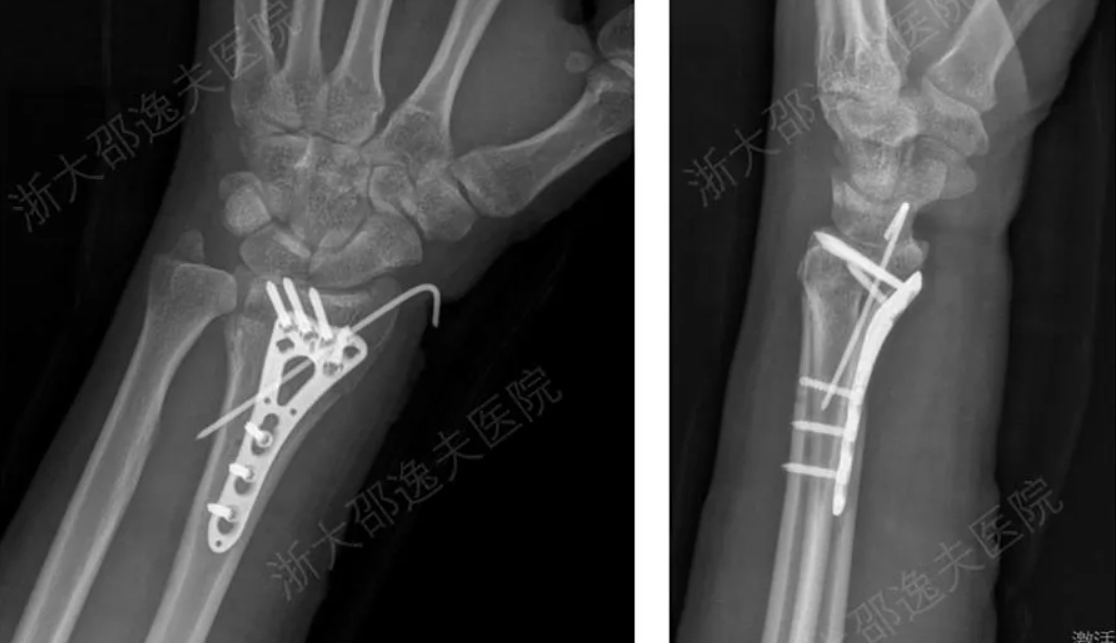

Một nhóm các nhà nghiên cứu Trung Quốc vừa công bố một loại keo y tế đột phá, có thể tiêm vào để gắn các mảnh xương bị gãy chỉ trong vòng ba phút. Loại keo mới này, có tên là Bone 02, được lấy cảm hứng từ khả năng bám dính phi thường của hàu dưới nước.

Các nhà nghiên cứu đã thiết kế loại keo sinh học này để mô phỏng vật liệu giàu protein và canxi cacbonat mà hàu tiết ra. Vật liệu này cứng lại nhanh chóng trong môi trường ẩm ướt, mặn và liên tục chuyển động. Bone 02 hoạt động hiệu quả tương tự bên trong cơ thể người, có thể gắn các mảnh xương bị vỡ trong 2-3 phút, ngay cả trong môi trường nhiều máu.

Theo báo cáo, vật liệu này đã được thử nghiệm trên hơn 150 bệnh nhân. Trong các thử nghiệm trong phòng thí nghiệm, keo cho thấy lực liên kết mạnh mẽ hơn 400 pound (khoảng 181 kg) và cường độ nén khoảng 10 MPa, cho thấy tiềm năng thay thế các thiết bị cấy ghép kim loại truyền thống như nẹp và vít.

Một ưu điểm lớn của Bone 02 là nó có thể tự phân hủy sinh học và được cơ thể hấp thụ một cách tự nhiên khi xương lành lại. Điều này loại bỏ nhu cầu phẫu thuật lần hai để tháo các thiết bị kim loại, giúp giảm thời gian phẫu thuật, đơn giản hóa các ca phẫu thuật chỉnh hình và giảm nguy cơ nhiễm trùng cùng các biến chứng khác.